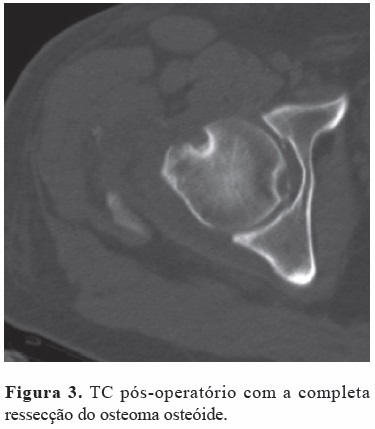

Após a cirurgia o paciente referiu alívio completo da dor prévia, e 13 meses após o procedimento não apresentava qualquer sinal de recorrência (Figura 3).

O “Non-arthritic hip score” (NAHS) pós-operatório da última reavaliação era de 100.